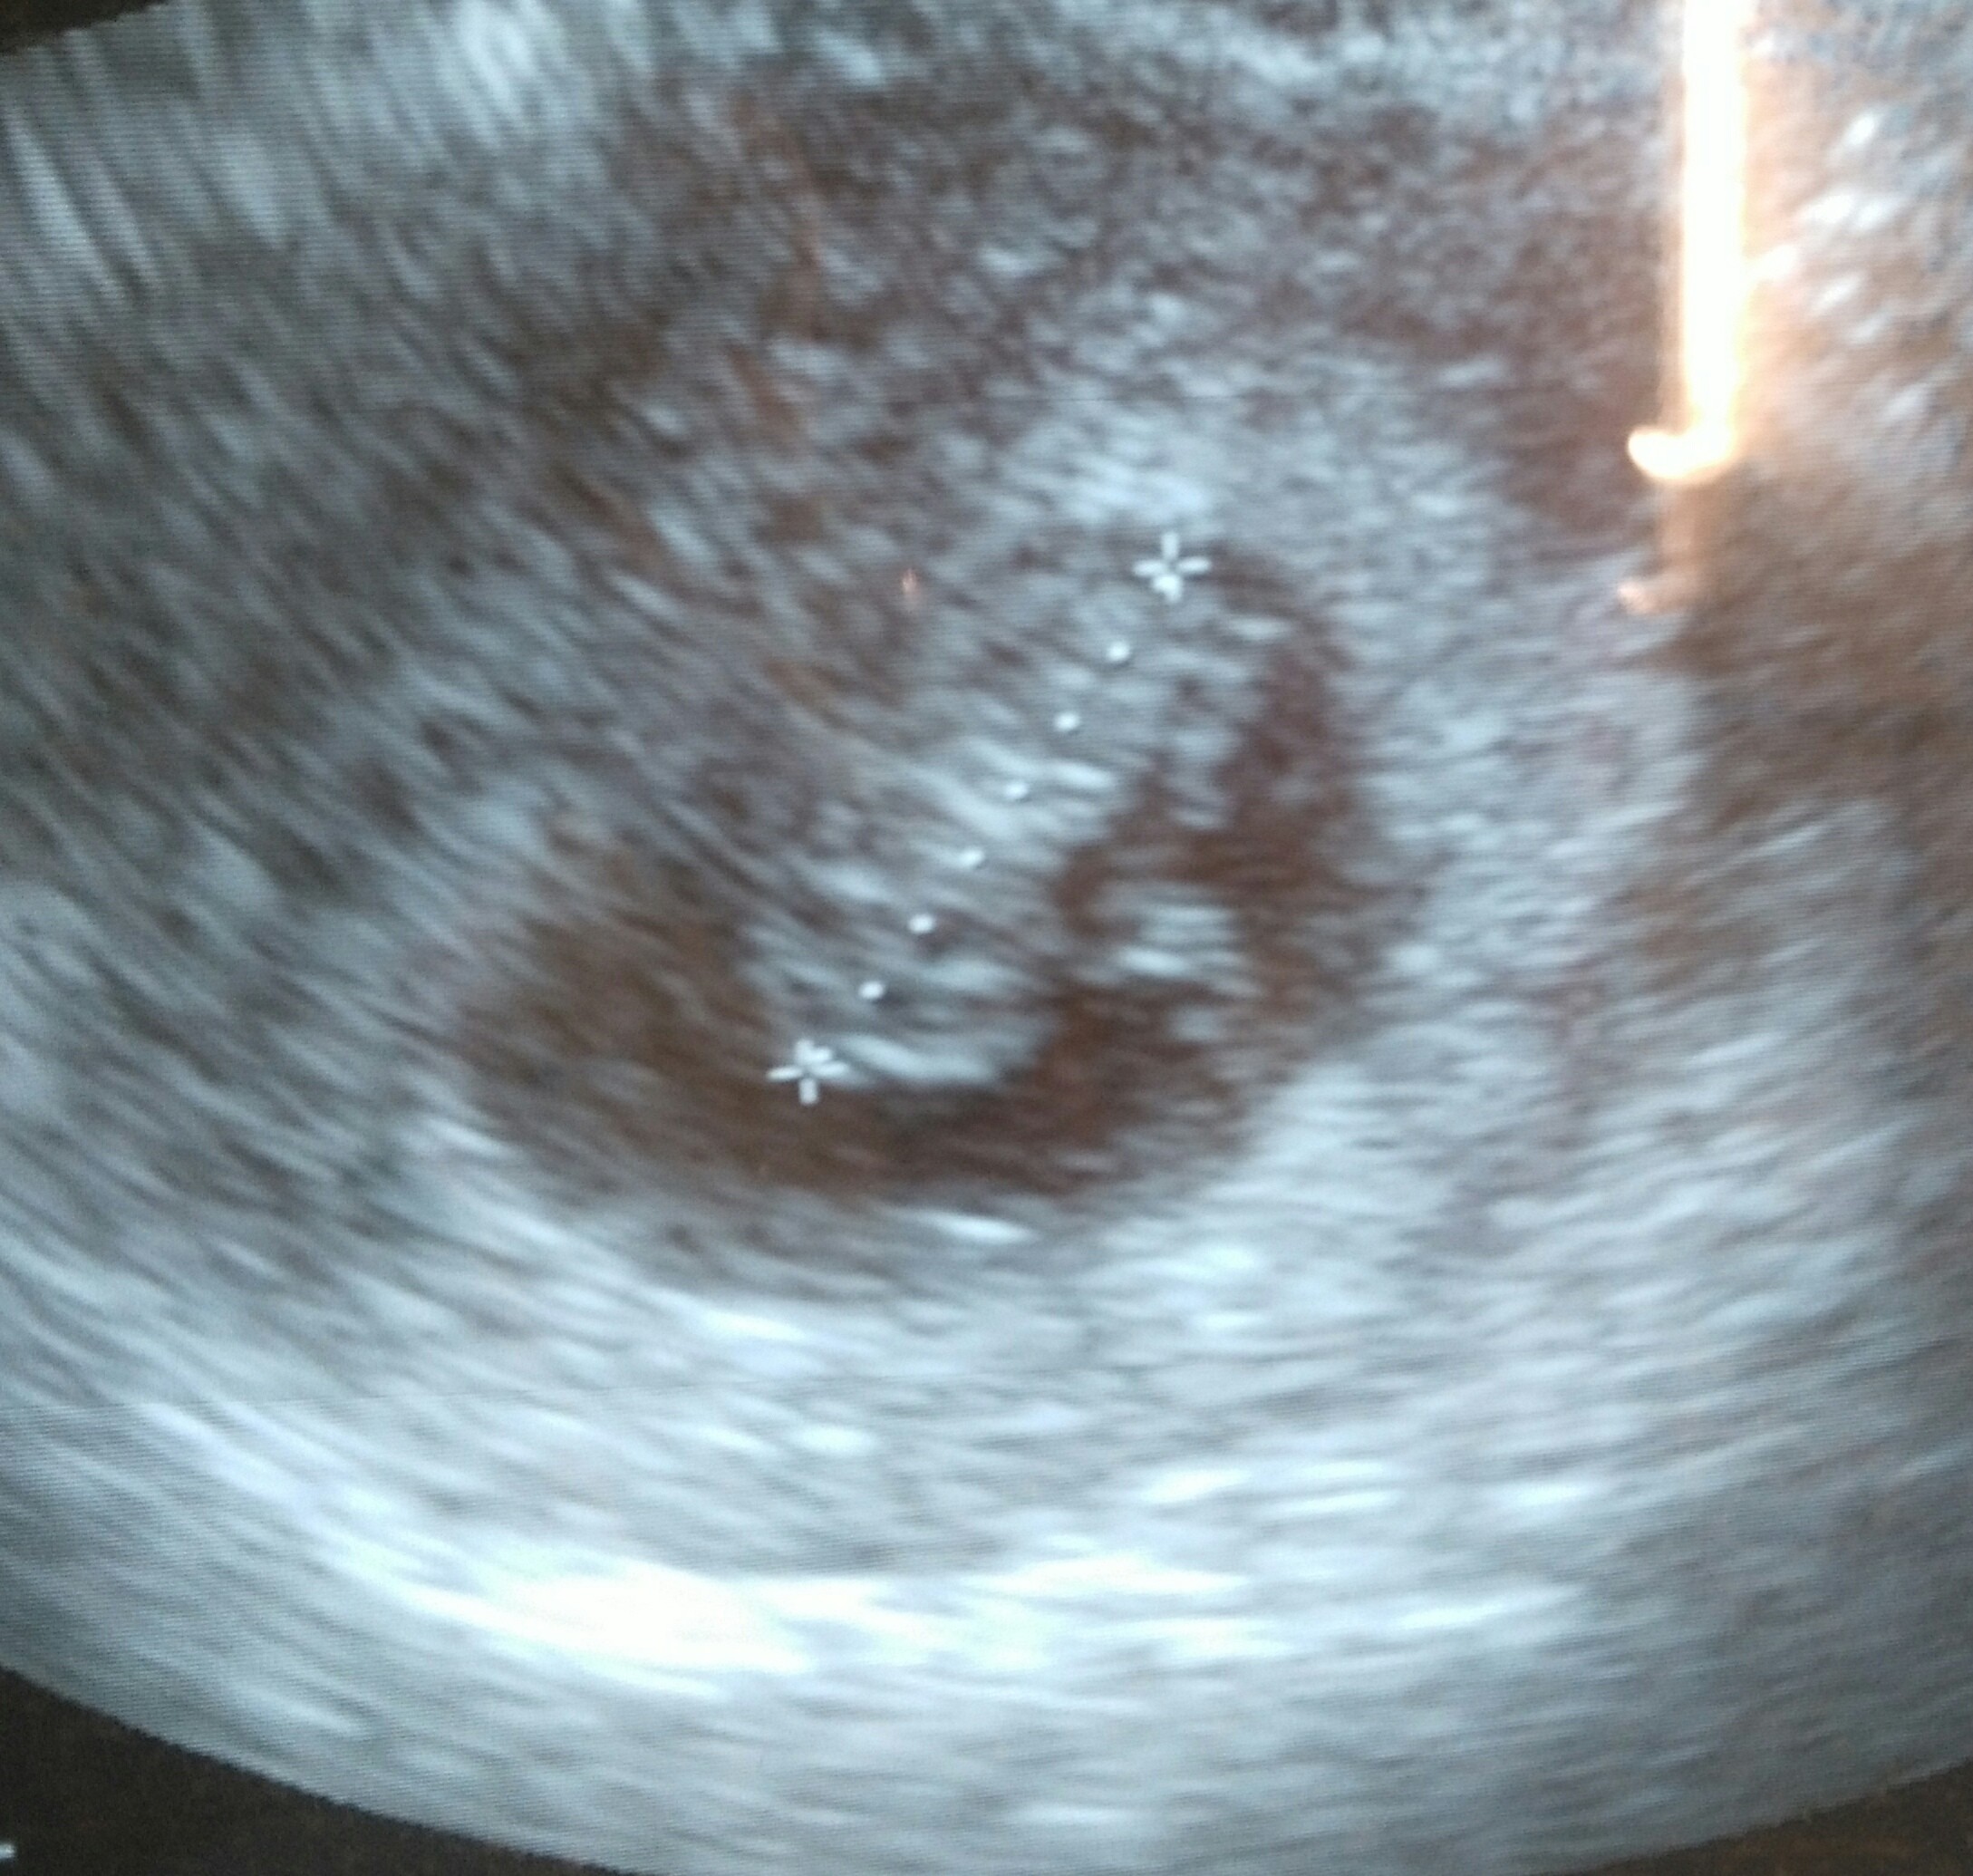

Hallo, Hallo! Mamy się świetnie! Nawet trochę się poruszałem(am) i pomachałem(am) rączkami i nóżkami :)Zobacz załącznik 864913

Super! Gratuluję [emoji173]